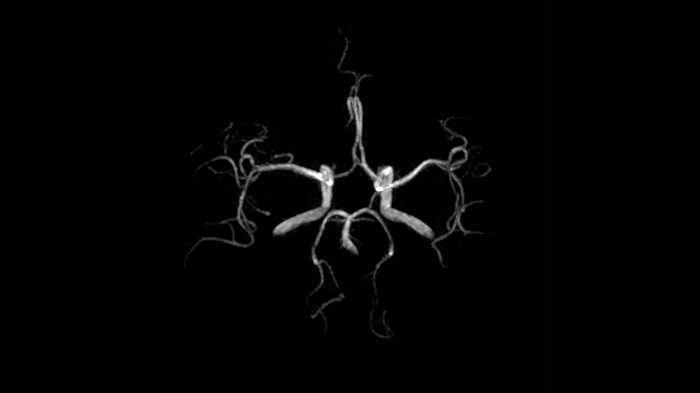

Time-of-flight angiography

To identify vessel occlusions or aneurysms, non-contrast enhanced angiography of the cranial vessels is supportive. High-resolution ToF angiography can also portray small arteries for delicate diagnoses.

0.4 x 0.4 x 0.5 mm2

TA 5:31 minutes

MAC-ID: 7aaaa0195.

MAC-ID: 7aaaa0195. Image Credit: Siemens Healthineers